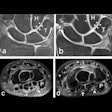

7T MRI shows renewed promise for imaging wrist trauma